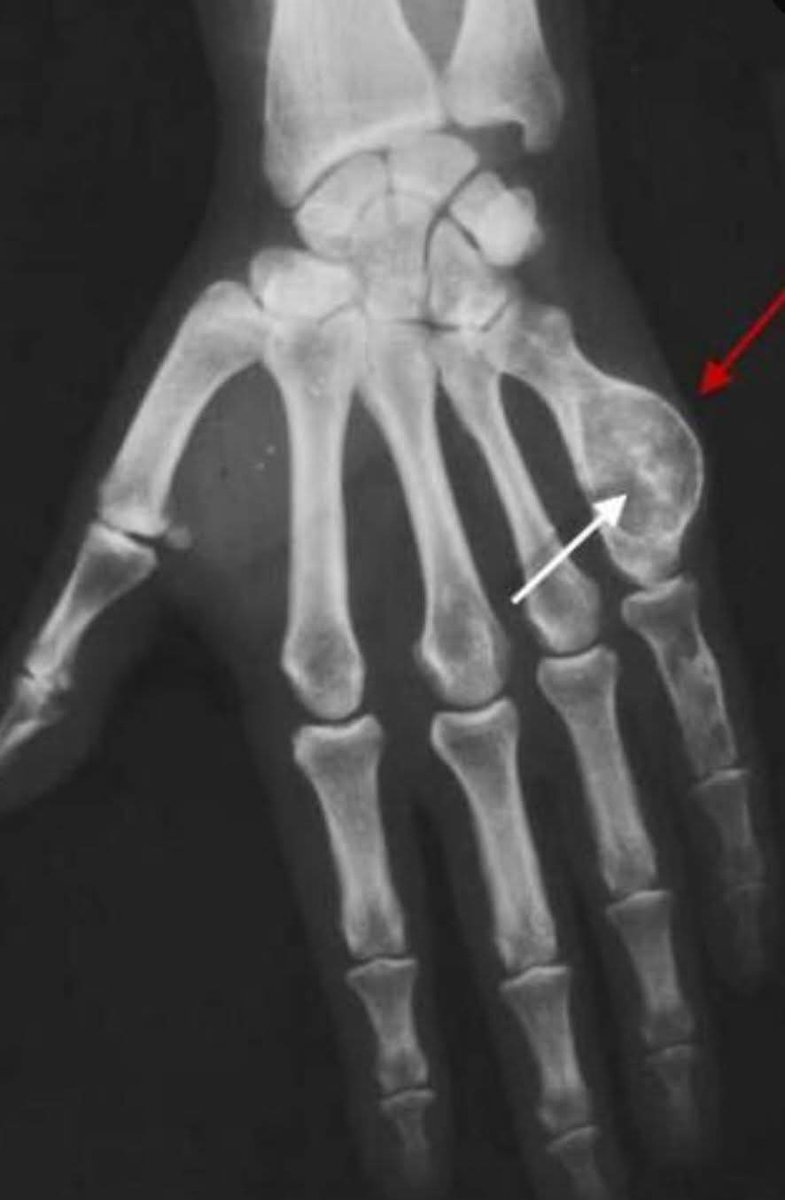

Fall on an outstretched hand with wrist pain… 👀 This is one of the most commonly missed fractures. You shouldn’t miss it on this xray. Can you name this fracture? Read: wikism.org/Scaphoid_Fract… #orthopedics #radiology #xray #mededucation #sportsmedicine #emergencymedicine

MedEd_Cases's tweet image. Fall on an outstretched hand with wrist pain… 👀

This is one of the most commonly missed fractures.

You shouldn’t miss it on this xray.

Can you name this fracture?

Read: wikism.org/Scaphoid_Fract…

#orthopedics #radiology #xray #mededucation #sportsmedicine #emergencymedicine